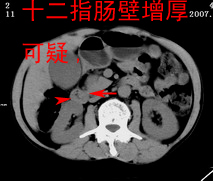

以下是引用zjzjr在2007-9-15 22:24:00的发言:[br]胰头钩突略饱满,肝内外胆管略扩张,胆囊积水.建议增强扫描.

以下是引用代课学生在2007-9-16 10:20:00的发言:[br]胆总管中段以上胆管均示扩张,考虑胆总管下段/胰头部病变,建议增强或micp检查。